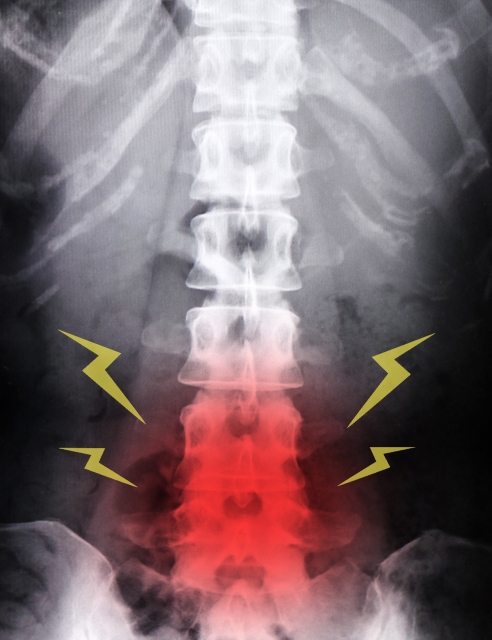

一般的に腰椎椎間板ヘルニアは、腰の骨の間にある椎間板というバームクーヘンのような構造をした線維輪の中心にあるゼリー状の髄核が椎間板を破って飛び出し、神経を圧迫することで痛みやしびれを引き起こす病気と言われています。発症の原因は、日常生活における腰への過度な負担の蓄積(前かがみ、重い物を持ち上げる、長時間の座り仕事)により発症すると言われています。

さらに、加齢による椎間板の弾力低下や、喫煙、遺伝的な要因も関係するとされています。

腰椎椎間板の症状は腰痛やお尻や足先に走る痛み、シビレ、間欠性跛行(数10m歩くと足に痛みやシビレが現れ、休憩を必要とする状態)などです。下肢の後面(ハムストリングス)が痛むことが多く、腰椎の5番だけに起きると下肢後面ではなく膝から下だけなど一部分のみが痛むこともあります。